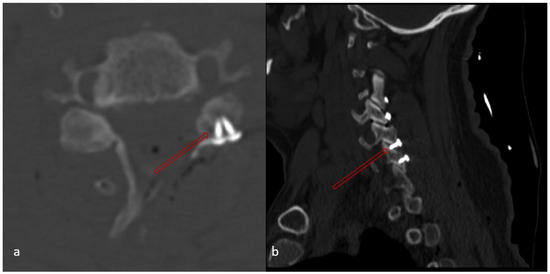

Background and Objectives: The assessment of cervical lordosis is essential for surgical planning and outcome prediction in patients with cervical spine pathology. This study aims to evaluate the accuracy of cervical lordosis measurements obtained on supine CT and MRI relative to standing [...] Read more.

Background and Objectives: The assessment of cervical lordosis is essential for surgical planning and outcome prediction in patients with cervical spine pathology. This study aims to evaluate the accuracy of cervical lordosis measurements obtained on supine CT and MRI relative to standing lateral radiographs. Materials and Methods: In this retrospective review, 108 patients who underwent standing lateral radiographs, supine CT, and MRI within a 30-day period were identified. C2–C7 Cobb angles were measured on each modality. Using upright radiographs as the reference standard, the predictive capability of both supine CT and supine MRI in classifying kyphotic versus non-kyphotic alignment was calculated. Results: Standing radiographs demonstrated significantly greater lordosis than supine imaging, with mean paired differences of 6.2° versus CT and 5.0° versus MRI (both p < 0.001); however, strong correlations were observed (with CT: r = 0.75; with MRI: r = 0.72; both p < 0.001). Further, CT-based measurements predicted X-ray Cobb angles with an R2 value of 0.57 (estimated X-ray Cobb angle = 8.24 + 0.74 × (CT Cobb angle), β = 0.74, p < 0.001). MRI-based measurements yielded an R2 of 0.51 (estimated X-ray Cobb angle = 7.59 + 0.71 × (MRI Cobb angle), β = 0.71, p < 0.001). At threshold ≥ 0°, CT achieved a 100% NPV for excluding kyphosis on upright radiographs. MRI achieved an NPV of 100% when the Cobb angle was >1.20°. Conclusions: Supine CT and MRI systematically underestimate cervical lordosis but demonstrate strong predictive correlation with standing radiographs and reliably exclude true kyphotic alignment, with each achieving near-perfect NPV at defined thresholds. In cases where standing radiographs are unavailable or nondiagnostic, supine imaging modalities such as CT and/or MRI, where the cervical region appears nonkyphotic, can safely rule out cervical kyphosis and inform surgical planning; however, in cases where the cervical region appears kyphotic on CT and/or MRI, standing radiographs remain essential for accurate assessment. Full article